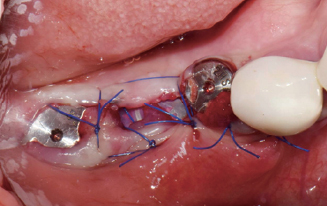

Membrane holding suture

봉합